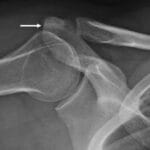

A healthcare professional will start with a physical examination. Diagnosis is confirmed using:

- X-rays (Zanca view): May show bone changes but often normal early on

- MRI scan: Identifies early bone damage and inflammation